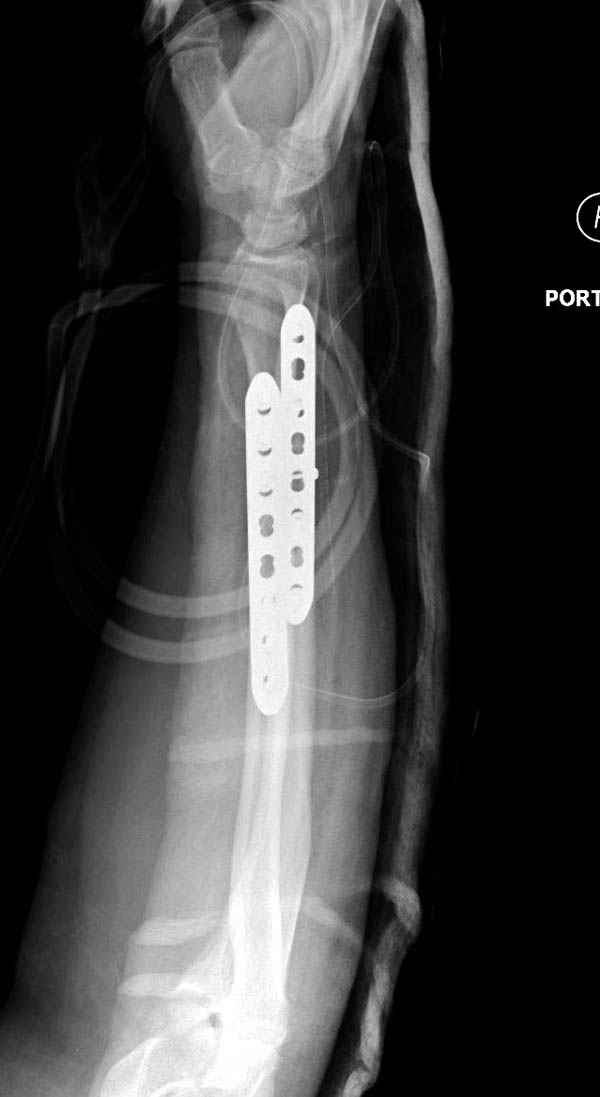

Второй случай, для лечения перелома проксимального

плеча применили пластину "Hand Innovation"

http://www.handinnovations.com/pdf/S3_technique.pdf

Пластина имеет преимущества перед другими "Locking

Implants", потому что пластину можно уложить намного ниже чем другие пластины и имеется возможности проведения шурупов под 130 градусным углом, таким образом можно уменьшить операционный разрез в проксимальной части.

Прооперирован вчера на 13 день после поступления.

Больному 41 и из-за гемодинамической нестабильности в течение первых 7 дней был в реанимации под интубационной седацией.

Извиняюсь за качества снимков, обычный больной в 300 фунтов, портативным ренген аппаратом не пробить.